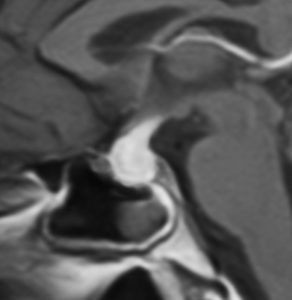

放射線が外れやすい部位は再発源となります

側脳室先端(前角,後角,側頭角,閂),下垂体と大脳基底核に放射線が入らないとその部位から再発します。

再発ジャーミノーマの画像です。延髄背側の閂 ovexという部位に再発しています。

このパターンはとても多いです。なぜかというと,全脳室照射の時に,第4脳室下端のovexの上衣 ependyum を照射野に入れない放射線治療医の先生がいるからです。放射線科の先生にもちょっとした知識が必要なのです。

これは再治療で腫瘍が消えても不可逆的な重症の延髄障害を残してしまいます。